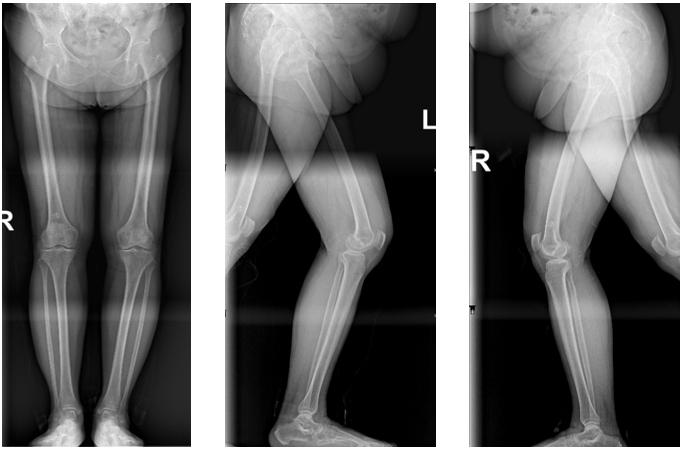

入院后,医护团队为王阿姨进行了全面的术前检查。结果发现,她长期膝痛的根源在于左膝的内翻畸形,也就是常说的“O型腿”。

进一步分析显示,这种畸形主要来源于胫骨侧。由于下肢力线的异常,使得她膝关节内侧的软骨面承受了过度的压力和磨损,从而引发了顽固性疼痛。

△ 术前X线